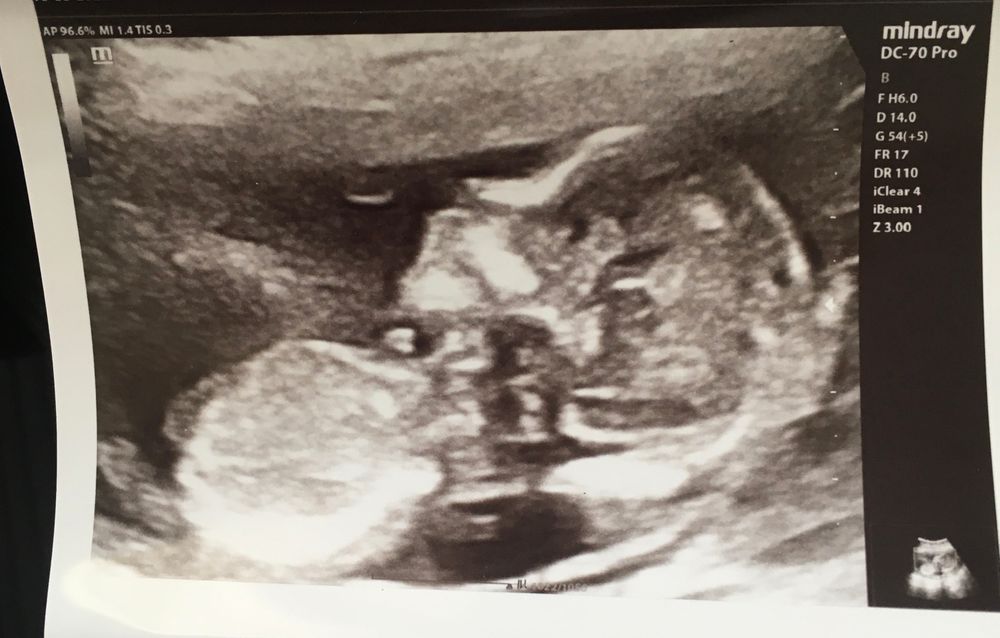

Miko в Благополучная беременность 4 года Половой бугорок Пол малыша Девочки, тут видно половой бугорок? Посмотрите еще 20 записей на эту тему Лучший ответ Margarita 😂это голова,мать 14.05.2022 Ответить Отменить Ответить Best mammy Конечно, сразу за подбородком 14.05.2022 Ответить Ксюша Дарья Тарасенко, 😂😂😂😂 14.05.2022 Ответить Tina На голове? 14.05.2022 Ответить Катерина 😂 Ну что за вбросы… это голова 14.05.2022 Ответить Anna Тут видно нос)) 14.05.2022 Ответить Чашка утреннего кофе Нет, это голова и часть грудной клетки, по-моему 14.05.2022 Ответить Наташа Нет. У нас на 12 неделе был виден, но было фото всего плода. 14.05.2022 Ответить Интересно🤔💭 Кому-нибудь говорили пол на 13 неделе и он был верным? Чаты Беременных Выберите чат: Январята-2026 Февралята-2026 Мартята-2026 Апрелята-2026 Майчата-2026 Июнята-2026 Июлята-2026 Августята-2026